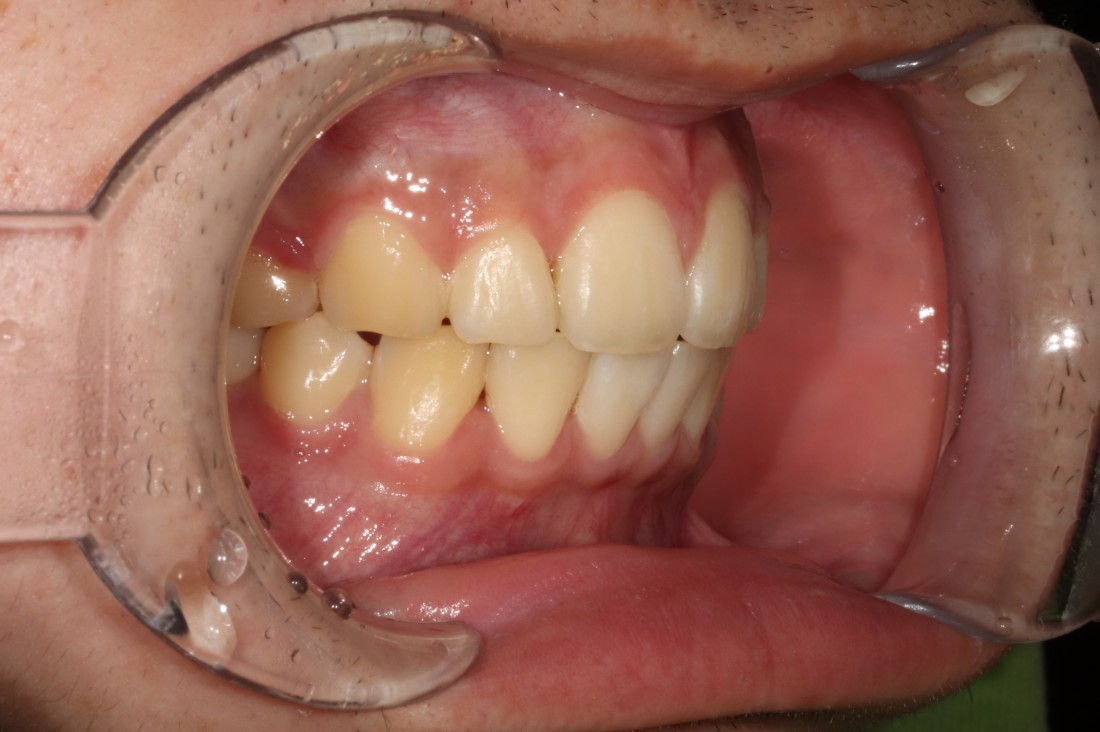

광주 개방교합 교정을 위해

방문해주신 30대 남성 환자분의

교정 전 사진입니다.

어금니를 맞닿게 하여서 입을 다물어도

윗니와 아랫니가 만나지 않는데요.